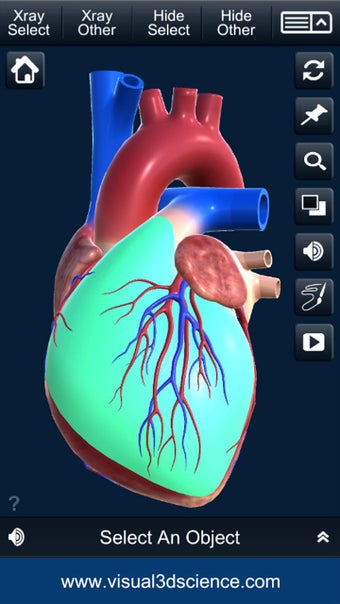

Es muy fácil de usar y muy interactiva. Puedes rotar 360°, hacer zoom y mover la cámara alrededor de un modelo 3D altamente realista.

Puedes seleccionar la vista de rayos X, ocultar y mostrar partes del corazón, así como ver animaciones en tiempo real, dibujar o escribir en la pantalla y compartir capturas de pantalla, pronunciación de audio para todos los términos de anatomía y más.